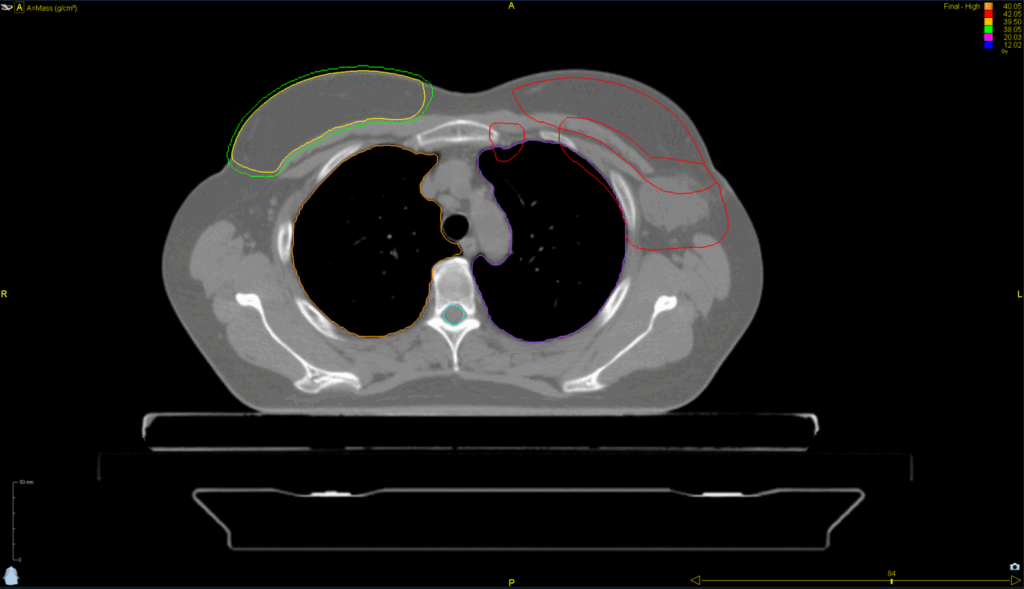

Complex Left Breast SIB and Nodes

< View All Plan Studies RADIXACT SYSTEM Complex Left Breast SIB and Nodes Case History AGE: 76-year-oldGENDER: Male Medical History Immidiate tolerance: Grade II dermatitis with eyelid edema, Grade I conjunctivitis resolved with Sterdex Diagnosis: Squamous cell carcinoma of the right lower eyelid Planning CT Images Treatment Plan Images ClearRT® Images Treatment Planning Highlights Fractionation […]